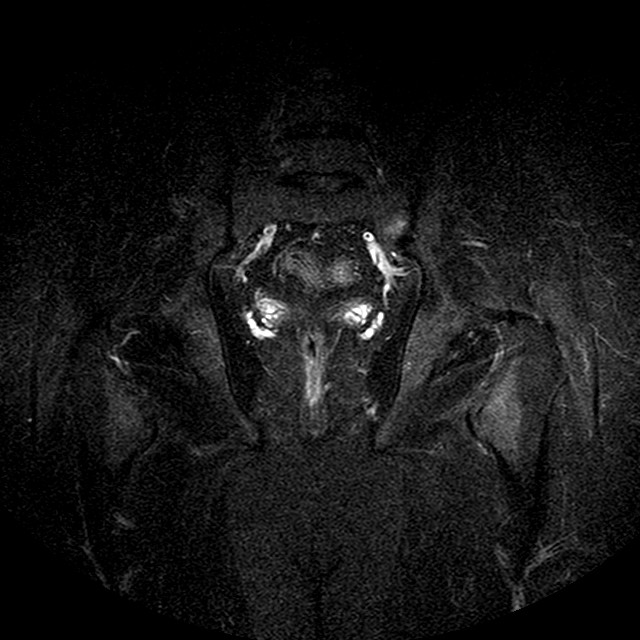

STIR

Evidenti e simmetriche alterazioni osteofitosiche in regione coxo femorale con riduzione delle rime articolari. Degenerazione completa del cercine glenoideo. Non attuali segni di versamento articolare. Non segni di edema osseo che escludono attuale algodistrofia od osteonecrosi. Lieve e simmetrica riduzione del trofismo della muscolatura glutea.